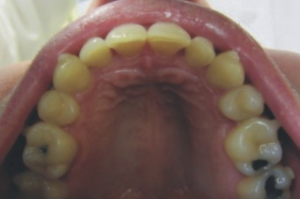

The patient had severe upper crowding. With a deep bite. We agreed to remove the 5/5 and provide Invisalign to close the gaps and correct the crowding. The aligners were changed every 2 weeks.

The back teeth were moved forward whilst the from teeth were moved backwards.